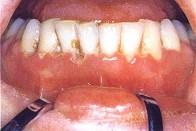

慢性溃疡性坏死性龈炎的主要表现()A.牙龈增生B.牙龈水肿C.附着龈增生D.牙间乳头消失E.游离龈消失

问题 慢性溃疡性坏死性龈炎的主要表现()

选项 A.牙龈增生 B.牙龈水肿 C.附着龈增生 D.牙间乳头消失 E.游离龈消失

答案 D